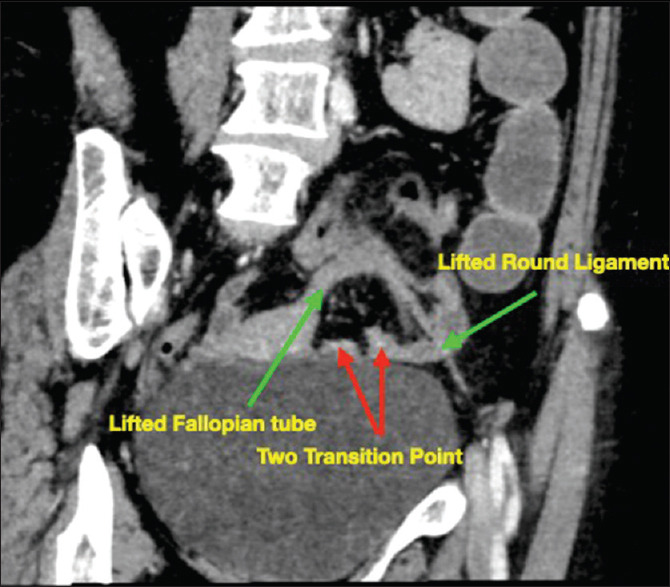

摘要:阔韧带疝(BLH)是一种罕见的内疝,如果不及时治疗可能会导致严重的并发症。在本病例报告中,我们介绍了一名女性患者的阔韧带疝病例,并讨论了其临床表现、诊断和处理方法。一名 40 岁的女性患者出现亚急性肠梗阻症状,包括无法排出胀气和粪便以及反复胆汁性呕吐。计算机断层扫描(CT)证实,左侧阔韧带内子宫附近有小肠梗阻。诊断性腹腔镜检查发现阔韧带内有一圈阻塞的小肠,将其释放后发现肠道健康。阔韧带和盆底韧带之间的缺损被缝合。患者恢复顺利,随访6个月后无任何症状。BLH可以是先天性的,也可以是后天性的,后天性缺陷通常是由于以前的手术或与妊娠有关的原因造成的。临床表现通常为肠梗阻症状,CT 扫描是首选的诊断方式,可显示闭环梗阻和肠扩张等特征性结果。腹腔镜手术具有恢复快、发病率低的优点。标准的手术方法是使用非吸收性缝合线缝合缺损,但也有将缺损切开的病例。手术有复发的可能,尤其是使用可吸收缝线缝合时。本病例报告强调了早期诊断和干预BLH以预防并发症的重要性,并强调了腹腔镜在治疗中的作用。

Abstract: Broad ligament hernias (BLHs) are rare internal hernias that can lead to serious complications if left untreated. In this case report, we present the case of a BLH in a female patient and discuss its clinical presentation, diagnosis and management. A 40-year-old woman presented with subacute intestinal obstruction symptoms, including the inability to pass flatus and faeces and recurrent bilious vomiting. A computed tomography (CT) scan confirmed small-bowel obstruction adjacent to the uterus within the left broad ligament. Diagnostic laparoscopy revealed a loop of obstructed small intestine within the broad ligament, which was released and found to be healthy. The defect between the broad and infundibulopelvic ligaments was closed with sutures. The patient had an uneventful recovery and was asymptomatic at a 6-month follow-up. BLHs can be congenital or acquired, with acquired defects often resulting from previous surgeries or pregnancy-related causes. The clinical presentation typically involves the symptoms of bowel obstruction, and a CT scan is the diagnostic modality of choice, showing characteristic findings such as closed-loop obstruction and bowel dilation. Laparoscopic management offers the advantages of faster recovery and less morbidity. Closure of the defect using nonabsorbable sutures is the standard surgical approach, although a wide opening of the defect has also been described. Recurrence is a possibility, particularly if absorbable sutures are used for closure. This case report highlights the importance of early diagnosis and intervention in BLHs to prevent the complications and emphasises the role of laparoscopy in their management.